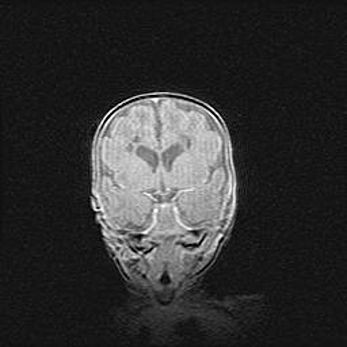

Мальформация Денди-Уокера. Киста задней черепной ямки.

Агенезия мозолистого тела.

Возраст: 2,5 месяца

Вес: 2420 г

Пол: женский

Окружность головы: 37 см

Срок гестации: 32 недели

Мальформация Денди—Уокера — редкий вид патологии ЦНС, представляющий собой врожденный порок развития каудального отдела ствола и червя мозжечка, ведущий к неполному раскрытию срединной (Мажанди) и латеральных (Лушка) апертур IV желудочка мозга. Для этогно синдрома характерна триада симптомов: гипотрофия червя мозжечка и/или полушарий мозжечка, кисты задней черепной ямки, гидроцефалия различной степени. В 70% случаев порок сочетается и с другими аномалиями головного мозга, в частности с агенезией мозолистого тела.